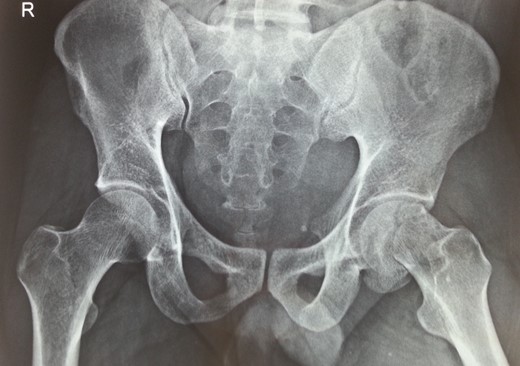

Following trauma patient had left-sided chest pain, frontal headache and severe pain in his left hip region. After hemodynamic stabilization and preliminary treatment for his chest and head injuries, he was evaluated for left hip region pain. Clinically patient had left anterior hip joint line tenderness. Initial X-ray imaging showed impacted subcapital fracture of femur neck, with varus angulation between femur head and neck (Fig. 1), which prompted detailed radiological evaluation. A 3D reconstructed CT scan imaging disclosed a separate fracture line in femur head, with a detached inferior head fragment (Fig. 2); thus, the patient had concurrent ipsilateral fracture of femur head and neck without hip dislocation. We decided to treat this fracture pattern surgically with either osteosynthesis and fixation, or primary total hip arthroplasty. Via posterolateral approach to hip, femur head and neck fractures were exposed. Proximal femur fragment showed severe impaction of cancellous bone, making chances femur head salvage with osteosynthesis precarious. Thus, we performed primary uncemented total hip arthroplasty (Fig. 3). Presently, the patient is 5 years post-surgery without any complaints and ambulates without support or limp.

Recent 5 years follow-up antero-posterior radiograph image of the patient with uncemented total hip arthroplasty prosthesis in situ.